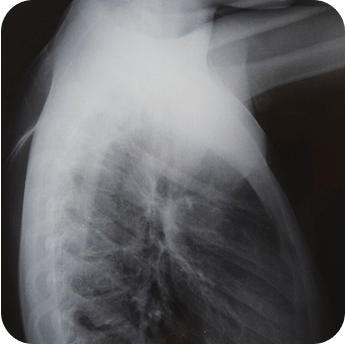

Результаты

До лечения

После лечения